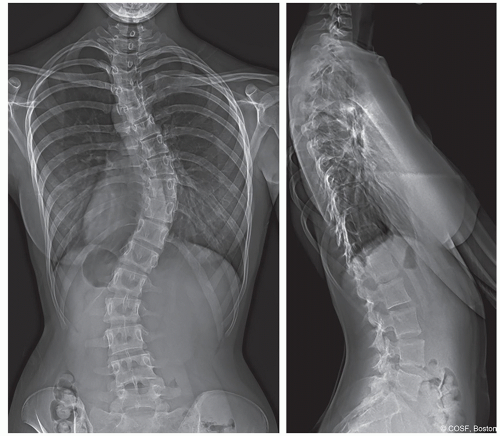

Typical adolescent idiopathic curve pattern is right thoracic with left lumbar and potential left upper thoracic curve (Figure 3.1)

Typical curves: Right thoracic, left lumbar